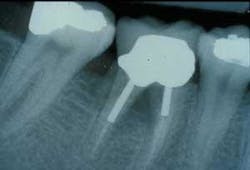

Furcation treatment of molars may include root amputation. The lowest success rate for root resection is found in mandibular distal root resections. Even when successful, to extract the distal root requires endodontics on the mesial root, core and crown of the mesial root, and the replacement of the distal root with an implant or fixed partial denture. An extraction of the entire molar and implant insertion has a higher success rate and often lower cost (see photos at right).

For example, multirooted endodontic therapy now approaches the cost of an implant surgery. When functional crown lengthening and endodontic post treatment is also required, the fees are usually greater than extraction and implant insertion. Treatment planning should take into consideration the natural tooth that requires periodontal therapy as well as multiple other aspects of treatment which compromise the long-term success and are cost prohibitive for the service provided.